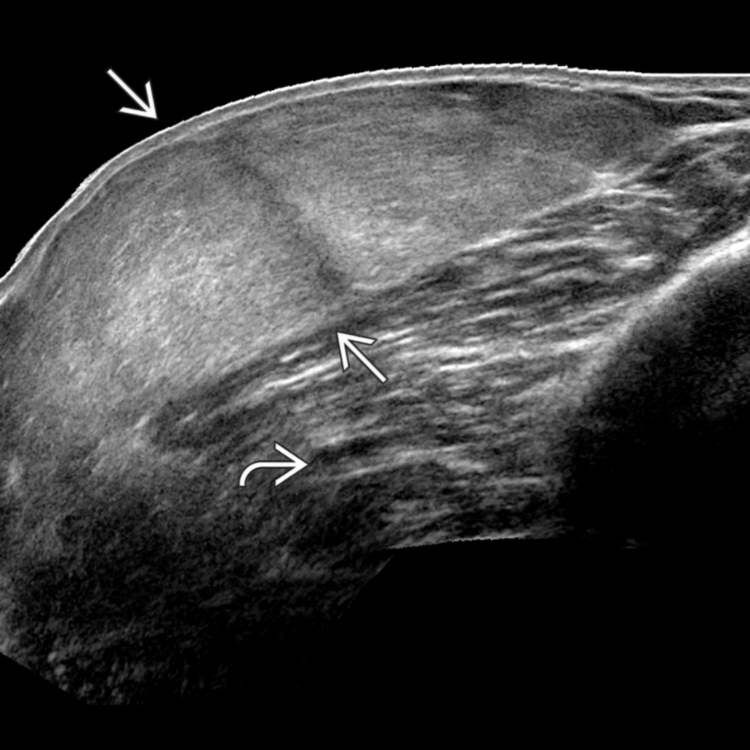

Lipoma of the spermatic cord. (a) US image demonstrates an echogenic …

Lipoma of Breast